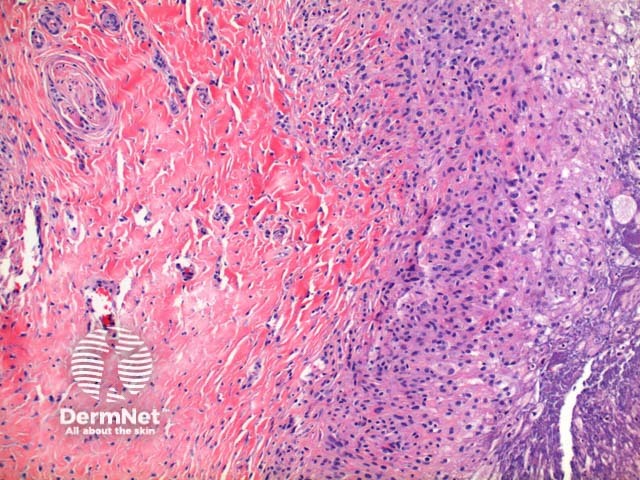

Scanning power view of phaeohyphomycosis shows a deeply extending granulomatous pattern (Figure 1) which may show areas of necrosis (Figure 2). Centrally an abscess or cystic nodule may form. Frequently a foreign body such as a wood splinter can be seen. The epidermis commonly shows pseudoepitheliomatous hyperplasia. The inflammatory infiltrate is comprised of histiocytes with multinucleated giant cells, and numerous neutrophils (Figures 3,4 and 5). At high power branching septate pigmented fungal hyphae can be seen (Figure 6).

Figure 5